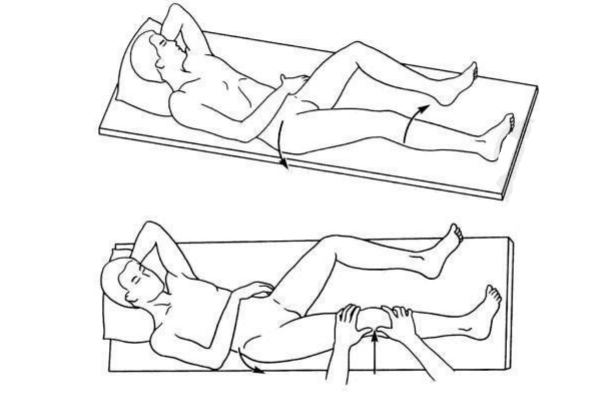

3、轴移试验

①Macintosh 轴移试验:

仰卧位,膝关节伸直,检查者一手拇指顶在被检查肢体的腓骨头后方向前施力,其余四指放在股骨远端前外侧向后向内施力使膝关节外展,另一手持足保持胫骨内旋外展,膝关节由伸直向屈曲活动。

当屈膝 20° ~ 40° 时,出现胫骨外髁向前半脱位,继续屈膝则自行复位为阳性。

②Slocum 轴移试验(侧方轴移试验):

人半侧卧位,被检查肢体在上,被检查足内侧紧贴检查台,膝关节伸直,检查者站立于患者背侧,双手拇指分别顶在关节线两端后侧,示指放在关节线两端的前侧,双手同时施加外翻前推力,在 25° ~ 45° 有脱位和复位为阳性。